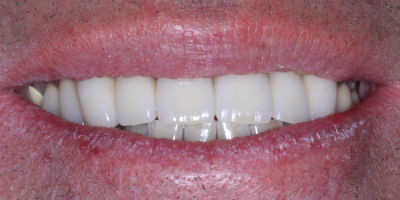

This is an advanced set of dental procedures best carried out by prosthodontists or restorative dentists. Full mouth rehabilitation is a term used in dentistry for rebuilding teeth and supporting structures after decay and gum disease has been stabilised. Full mouth rehabilitation is only required if your bite has collapsed or you have multiple missing or heavily filled teeth. Implants, crown and bridgework and/or partial or full dentures can be used to restore your bite close to its original height. Temporary restorations or dentures are used to get an idea of what the final result will be like before having the final restorations made. Temporary restorations also allow you to have input into your appearance and smile giving you the opportunity to show friends and family what your teeth may look like when the work is complete.

Before/After